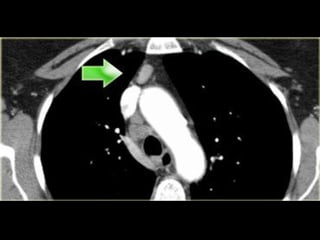

3. Prevascular & prevertebral LNs

• Prevascular LNs (3A) are located anterior

to the vessels.

• Prevertebral (retrotracheal) LNs (3B) are

located anterior to the spine.

• Prevertebral LNs are not accessible

through mediastnioscopy but only

available through Endoscopic U/S.